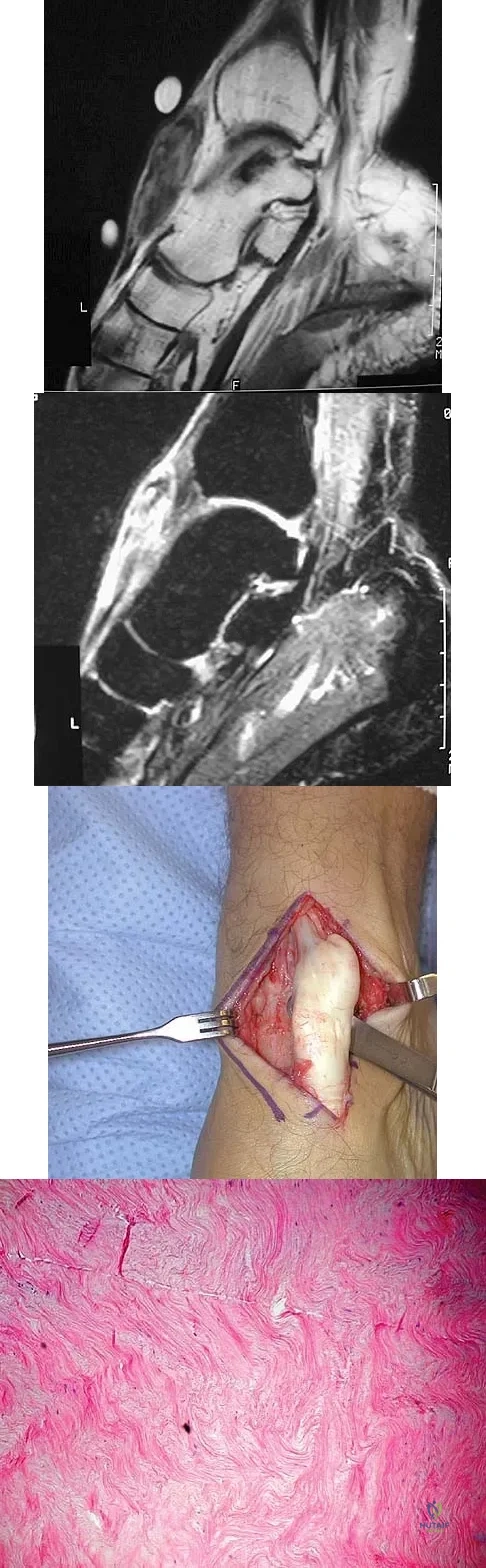

A 40-year-old man has a painful mass on his anterior ankle joint with limited range of motion. A radiograph, MRI scan, a gross specimen, and a hematoxylin/eosin biopsy specimen are shown in Figures 5a through 5d. What is the most likely diagnosis?

A 40-year-old man has a palpable mass over the dorsum of the ankle. He reports no history of direct trauma but notes that he sustained a laceration to the middle of his leg 6 weeks ago. Examination reveals a 4-cm x 1-cm mass. T1- and T2-weighted MRI scans are shown in Figures 12a and 12b. An intraoperative photograph and biopsy specimen are shown in Figures 12c and 12d. What is the most likely diagnosis?